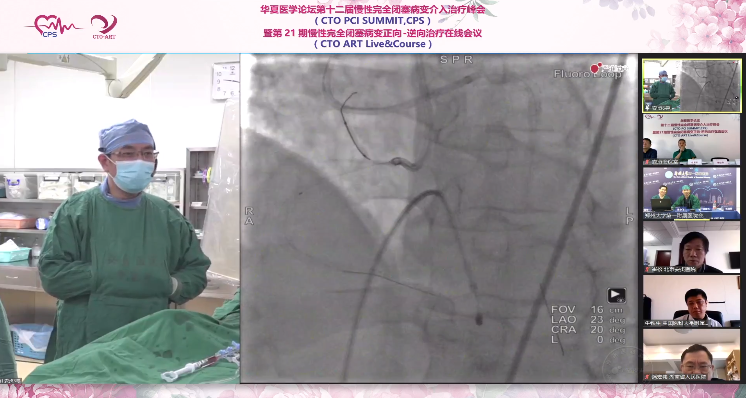

2.对RCA进行尝试开通,使用Pilot50导丝在Corsair微导管辅助下尝试Knuckle,但闭塞段过硬,无法前进,升级Pilot200导丝进行推进,但指引导管支撑力不够无法前进,加用边支锚定增加支撑力后,Pilot200可逐渐至支架远段,送至后降支,但Corsair微导管无法通过,尝试使用1.5mm球囊扩张,但球囊通过困难,使用爆破球囊技术也仅将球囊送至RCA中段。

专家建议:球囊无法通过第二转折,可先尝试更换角度,了解支架和导丝的位置关系,评估导丝是否位于支架内,也可尝试使用另一导丝再次通过闭塞段更换路径。必要时可尝试使用准分子激光治疗。